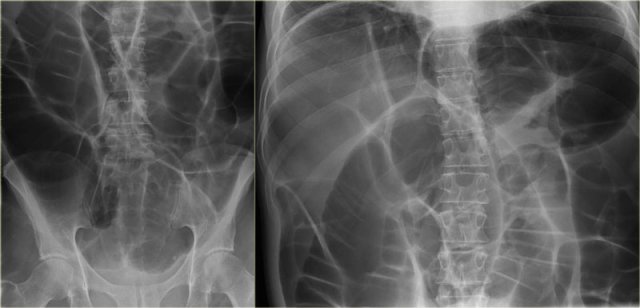

Here another sigmoid volvulus.

On the abdominal x-rays it is difficult to recognize what is going on, since so many bowel loops are dilated.

Continue with the CT-images.

CT is very helpful in this case and demonstrates the twist at the transition point (arrow).

The last image shows the collapsed rectum posterior to the dilated small bowel loops.

In the pelvis dilated small bowel loops were seen and a collapsed distal sigmoid (arrow).